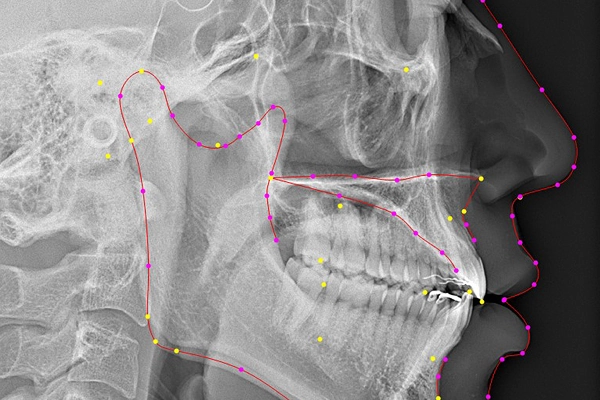

セファロ分析による

将来の成長を見据えた

矯正計画

セファロ分析(頭部X線規格写真)は、顔の骨格や歯の角度、顎の成長などを分析する検査です。ラクーンデンタルクリニックでは、このデータをもとにお子さまの成長を予測し、今後の歯並びの変化を見据えた治療計画を立てます。矯正治療の前後で比較することで、効果の確認や治療方針の見直しにも役立ちます。